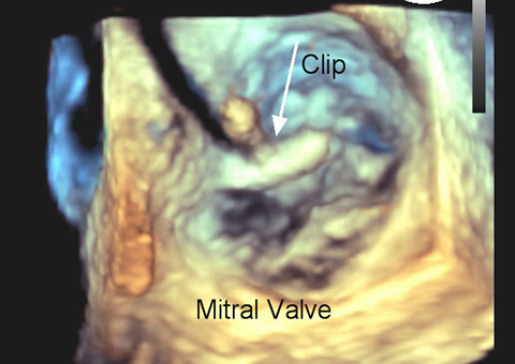

Multidisciplinary Team Performs Minimally-Invasive Transcatheter Mitral Valve Repair